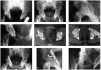

Figuras 9a-e

a) Paciente de 28 años de edad con luxación posterosuperior derecha tras colisión frontal. Se visualizan el defecto de la pared posterior y el desplazamiento del fragmento posterosuperior

b) Proyección obturatriz. Mejor visualización del defecto de la pared posterior y del fragmento desplazado.

c) Imagen de tomografía computarizada (TC) del techo acetabular. Se observa el fragmento de la pared posterior.

d) Imagen de TC más distal que permite la identificación del fragmento de la pared posterior y la luxación de la cabeza femoral.

e) Resultado a los 18 meses de la intervención. Osteosíntesis interna con 3 tornillos deslizantes de medianos fragmentos del fragmento de la pared posterior. Osificaciones periarticulares tipo III según la clasificación de Brooker1. Puntuación de Merle d'Aubigné de 14 puntos.